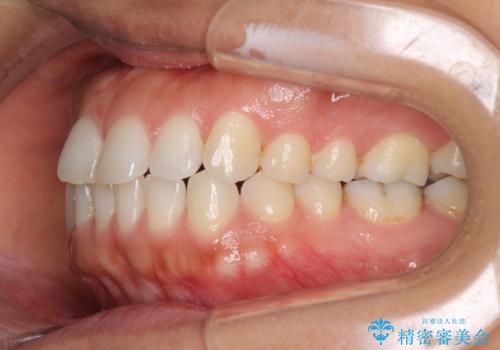

受け口傾向の前歯 すきっ歯の改善

- 前歯の隙間と口元の突出感を気にして来院された患者様です。

嚥下時に舌を突出させる癖があり、成長期に下顎が有意に成長し、歯と歯の間に隙間ができてしまいました。

舌の癖を改善し、インビザラインにて治療を行うこととしました。

舌癖を改善したことで、隙間や突出感を改善することができました。

隙間は後戻りしやすいため、舌側を細いワイヤーで固定することとしました。